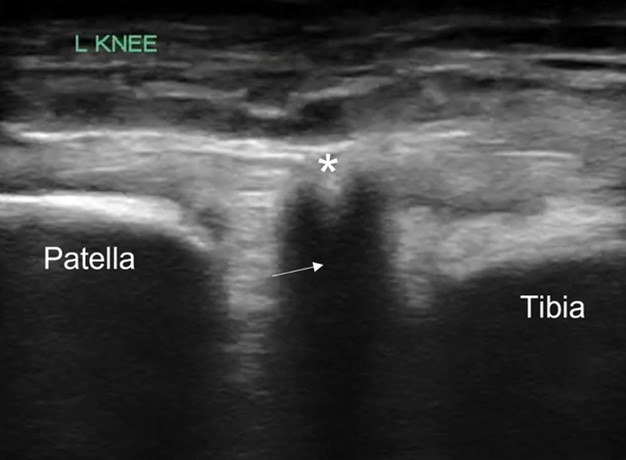

POCUS of the left knee was performed, which was concerning for a patellar tendon rupture and a joint effusion. (Figure 1 and Video 1) In addition, there was posterior acoustic shadowing obscuring part of the patellar tendon concerning for an avulsed bony fragment. (Figure 2) X-rays were performed, which confirmed the suspected diagnosis of a left tibial tubercle avulsion. (Figure 3) The patient was ultimately taken to the operating room for an Open Reduction and Internal Fixation (ORIF) by Orthopedic Surgery and discharged home the following day in a knee brace.

Figure 2. Patellar tendon with focus of acoustic shadowing (arrow) concerning for avulsed bony fragment (*)

In our case report, we successfully identified key features suggestive of tibial tubercle fractures: disruption of the patellar tendon, posterior acoustic shadowing of a bone fragment, and a large joint effusion. To perform knee ultrasound, the linear probe should be used and placed inferior to the patella in sagittal plane. The patellar tendon should be visualized in two planes, fanning through it completely (Video 1), and compared to the contralateral normal knee. (Figure 4) Abnormal findings suggestive of epiphyseal fractures include disruption of the tendon, an increased hypoechoic space adjacent to or posterior to the tendon (suggestive of either hemarthrosis or a hematoma), or a hypoechoic zone (ie, posterior acoustic shadowing due to an avulsed bony fragment).3,4

Figure 4: A) Ruptured tendon (arrow) in comparison against (B) contralateral knee indicating the normal continuous tendon fibers (arrow)